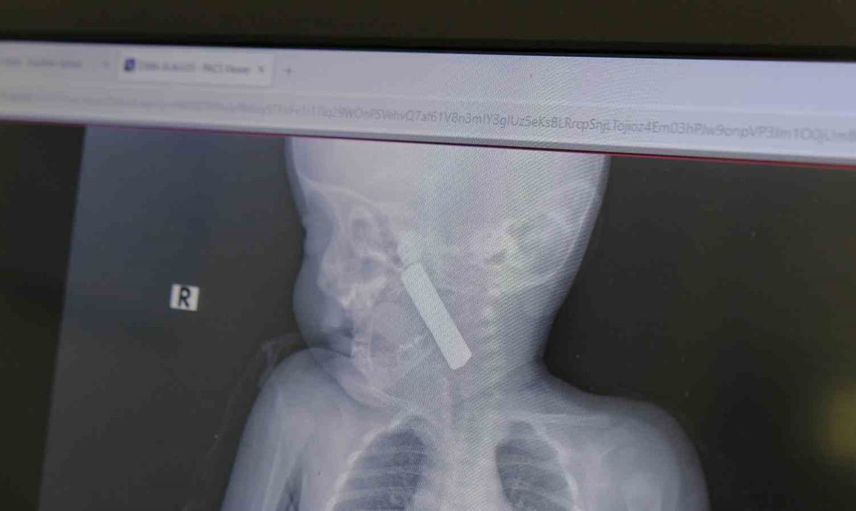

Karaman Eğitim ve Araştırma Hastanesi acil servisine kusma şikayetiyle getirilen 6 aylık E.A. isimli kız bebekte yapılan muayene ve tetkiklerde, boğazına kumanda pili kaçtığı tespit edildi.

Bebekte solunum sıkıntısı gözlenirken hastanın oksijen satürasyonu yaklaşık 90 civarındaydı ve siyanotik görünüm mevcuttu. Durumun ciddiyeti üzerine bebek vakit kaybetmeden ameliyata alındı.

Çocuk Cerrahisi Uzmanı Doç. Dr. Mehmet Uysal başkanlığındaki ekip tarafından yapılan operasyonda, anestezi ekiplerinin entübasyonunu takiben laringoskop ve magill forseps kullanılarak yabancı cisim çıkarıldı.

Doç. Dr. Mehmet Uysal olayla ilgili, "Acil polikliniğimize kusma şikayeti ile 6 aylık bir kız bebek getirilmiş ve bize haber verildi. Biz de vakit kaybetmeden geldik, hastamızı gördük. Yapılan tetkikler sonucunda, ağız tabanına oturan ve yemek borusunun birinci darlığına kadar uzanan, kumanda pili dediğimiz bir pille karşılaştık. Filmde ve muayenede bunu gördük. Hastayı ilk gördüğümüzde bayağı siyanotik durumda, solunum sıkıntılıydı ve oksijen satürasyonu 90 civarındaydı. Böyle olunca bir an önce beklemeden hızlı bir şekilde ameliyathaneye götürdük. Orada ameliyathanedeki anestezi uzmanlarımız ve personel bize yardımcı oldu, hasta hızlı bir şekilde entübe edildi. Ondan sonra da laringoskop ve magill forseps dediğimiz malzemelerimizle bu yabancı cismi çıkarmış olduk. Bir an evvel müdahale ettik, iyi ki müdahale ettik, orada ağız tabanında, özellikle ön kısmında hasar oluşmuştu. Müdahale sonrasında da hastanın solunum problemleri bir süre devam etti, bu yüzden 24 saat takip ettik. Herhangi bir problem oluşmayınca 24 saat sonra kontrole gelmek üzere hastayı taburcu ettik," dedi.